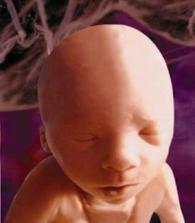

Druhé tři měsíce těhotenství jsou pro spoustu žen nejkrásnějším a nejpříjemnějším obdobím za celou dobu těhotenství.

S blížícím se koncem těhotenství se zvyšuje i netrpělivost. Objevuje se obava ze samotného porodu a z faktu příchodu nového člena rodiny.